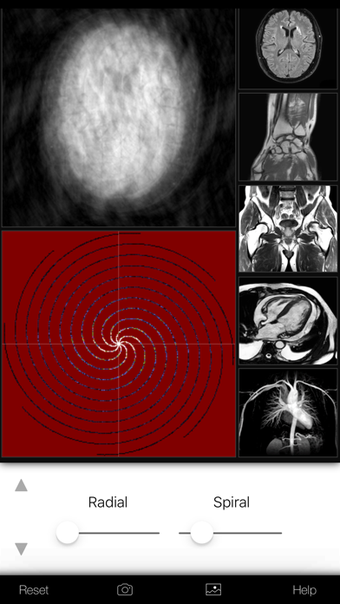

Een volledige versie app voor iPhone, door Eltjo Haselhoff.

A K-Space Odysseyis een app met volledige versie voor iPhone, die deel uitmaakt van de categorie ' Geneeskunde'.

Over A K-Space Odyssey voor iPhone

Een K-Space Odyssey is beschikbaar voor iOS 12.1.2 of hoger. De huidige versie van de software is 1.9.1 en u kunt deze alleen in het Engels krijgen.